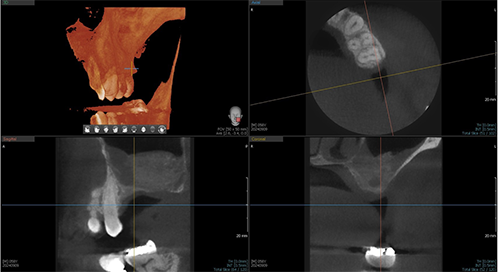

At the four-month healing evaluation, a new CBCT scan was taken to assess bone regeneration and plan for implant placement (Fig. 3). The bone height had increased to 13 mm, with a width of 8 mm—sufficient for placement of a 6.0 × 10 mm MegaGen implant. The soft tissue appeared healthy, and the patient was scheduled for implant placement in two months.

Elevating Implant Success

Fig. 3